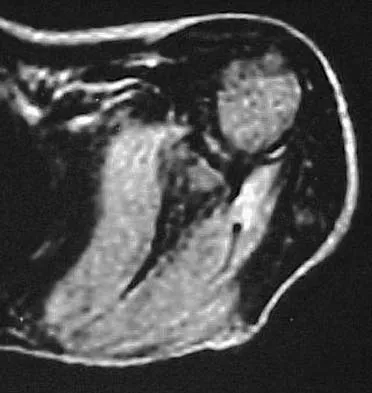

Question 91

A 65-year-old man with ankylosing spondylitis sustains an extension injury to his cervical spine. Two days later, a progressive neurologic deficit develops at the C6 level. An MRI scan is shown in Figure 1. What is the most likely diagnosis?